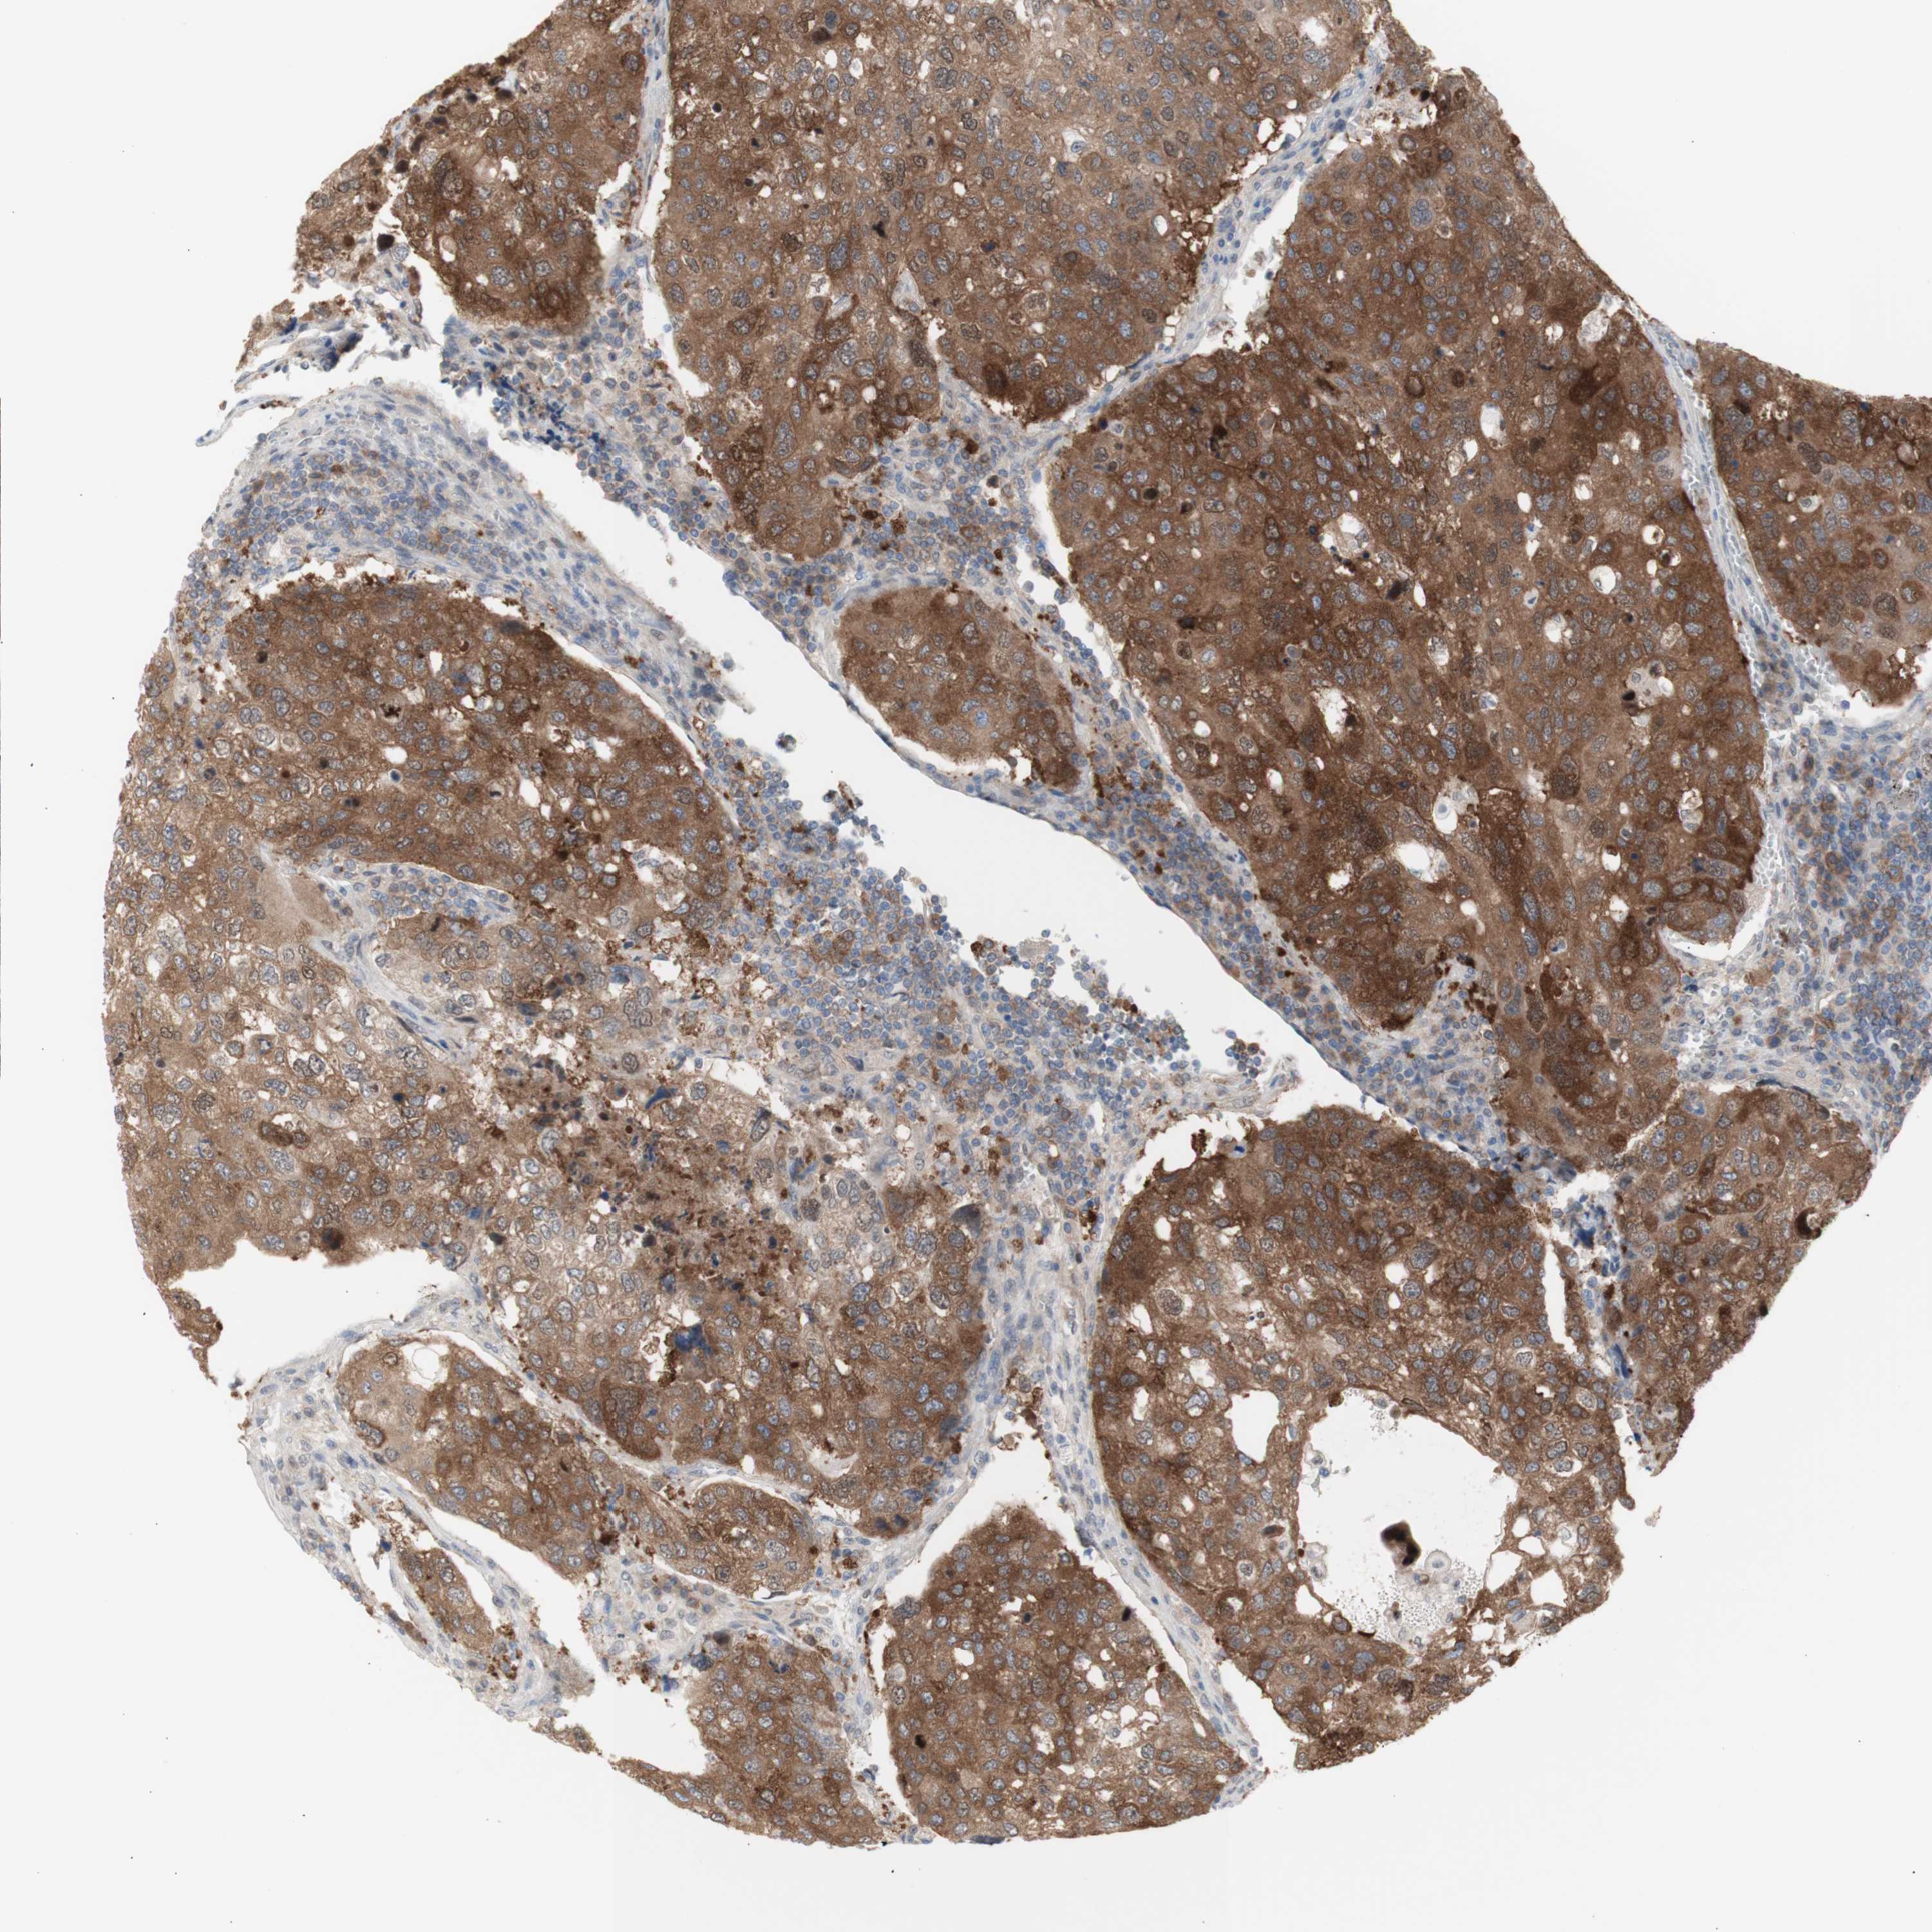

UROTHELIAL CANCER - Protein expressioni

A mouse-over function shows sample information and annotation data. Click on an image to view it in a full screen mode. Samples can be filtered based on level of antibody staining by selecting one or several of the following categories: high, medium, low and not detected. The assay and annotation is described here.

Note that samples used for immunohistochemistry by the Human Protein Atlas do not correspond to samples in the TCGA dataset.

Antibody stainingi

Antibody staining in the annotated cell types in the current human tissue is reported as not detected, low, medium, or high, based on conventional immunohistochemistry profiling in selected tissues. This score is based on the combination of the staining intensity and fraction of stained cells.

Each image is clickable and will lead to virtual microscopy that enables deeper exploration of all samples and also displays staining intensity scores, fraction scores and subcellular localization as well as patient and tissue information for each sample.

Antibody HPA005525

Antibody HPA064708

Antibody CAB012459

Staining

High

Medium

Low

Not detected

Intensity

Strong

Moderate

Weak

Negative

Quantity

>75%

75%-25%

<25%

None

Location

Nuclear

Cytoplasmic/membranous

Cytoplasmic/membranous,nuclear

Urothelial carcinoma, Low grade